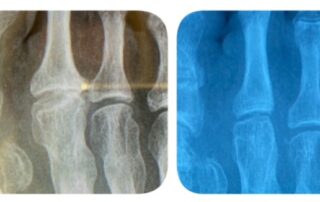

Enfermedad de Freiberg o osteocondritis del metatarsiano del pie.

La enfermedad de Freiberg o Koheler II es una necrosis avascular de la cabeza del metatarsiano.

La causa es multifactorial, siendo la sobrecarga o agresión traumática repetitiva y una afectación vascular, las más habituales.

Normalmente afecta más en la mujer siendo una